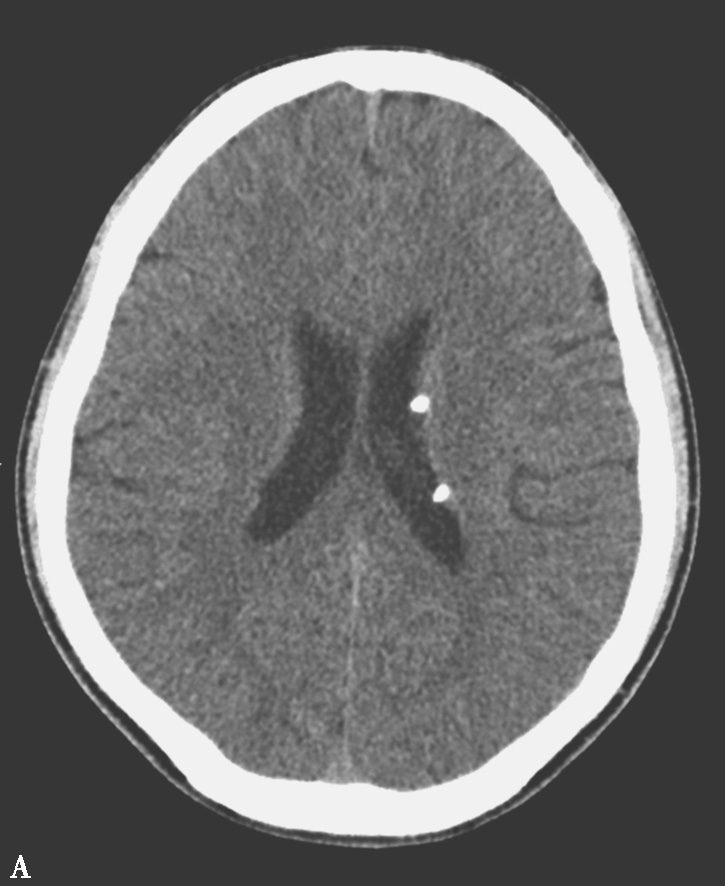

图1-6 结节性硬化

A、B.CT平扫,示双侧侧脑室室管膜下可见多发钙化结节,部分突入脑室内